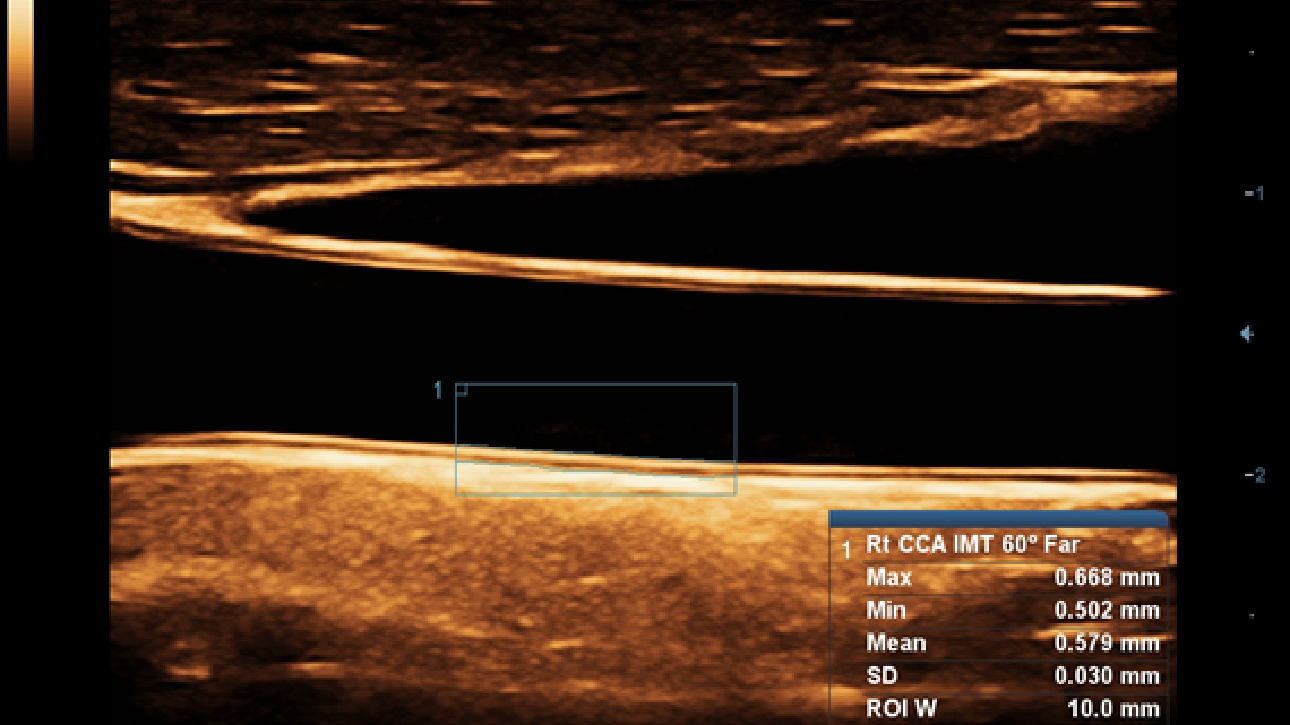

X-Insight, daha geli?mi? g?rĂŒntĂŒler elde etmek i?in kapsaml? bir ??zĂŒmdĂŒr.

Mindrayâin yeni ??zĂŒmĂŒ, geli?en en yeni ultrason teknolojileri ile birlikte, mĂŒ?terilerin g?rĂŒ?lerini klinik gerekliliklerle tam anlam?yla birle?tiren bir ??zĂŒmdĂŒr. Taptaze bir ruhla, gelece?e odaklanarak ve s?n?rs?zl???n pe?inde ko?arak, artan ?l?eklenebilirlikte sĂŒrekli olarak geli?en bir ??zĂŒmdĂŒr.

?ok y?nlĂŒ bir partner olarak, X-Insight'l? DC-60 Exp, her y?nĂŒyle gĂŒnlĂŒk klinik uygulamay? kolayl?kla ve belirsizlik olmadan y?netmenize yard?mc? olacak kapsaml? bir ??zĂŒm sunar.

MĂŒ?teri gereksinimlerine y?nelik g?rĂŒ?ler temelinde, X-Insight'l? DC-60 Exp, eXpress Clarity, eXceptional Intelligence ve eXceeding Experience ile gĂŒ?lendirilerek, hassas g?rĂŒntĂŒlemeyle yĂŒksek verimlilik sa?layacak ?ekilde tasarlanm??t?r.